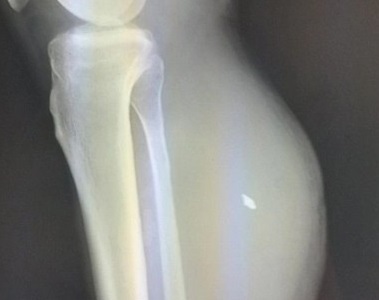

Во время обследования в правой голени мужчины обнаружили пятимиллиметровый осколок, которым была повреждена малая берцовая артерия. Также у пациента образовалась посттравматическая ложная аневризма объемом 500 миллилитров.

Фото - УОКБ